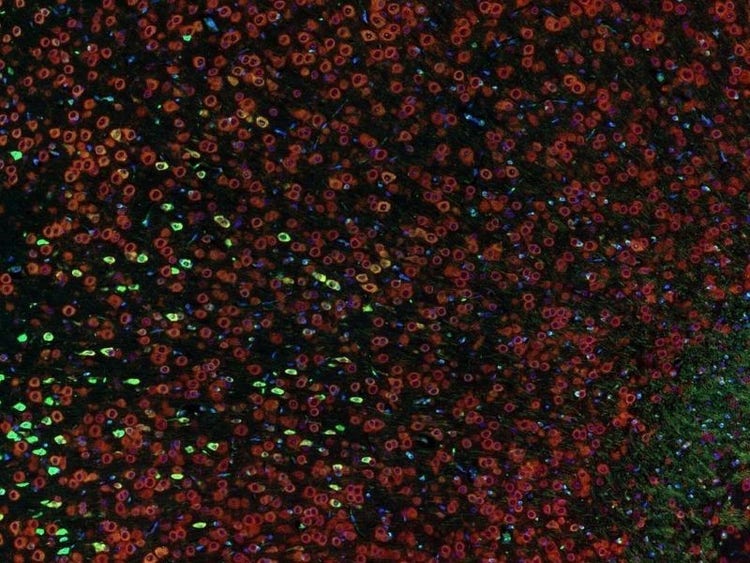

Fluorescence imaging of a mouse brain

これらの画像は一つひとつが独立した拡大画像に見えますが、すべて合わせると、蛍光イメージングで撮影されたマウスの脳の画像が形作られます。

イギリスの科学者、George G. Stokes卿は、蛍石に紫外線を当てると蛍光を発することを最初に発見し、「蛍光」という用語を作りました。Stokes卿は、蛍光は励起光よりも波長が長いことに気づき、今日では、この現象はストークスシフトとして知られています。蛍光顕微鏡法は、自然のまま(一次蛍光または自家蛍光と呼ばれます)か、蛍光を発することのできる化学物質で処理した場合(二次蛍光として知られています)かのいずれかで蛍光を発することのできる物質を研究するための優れた方法です。